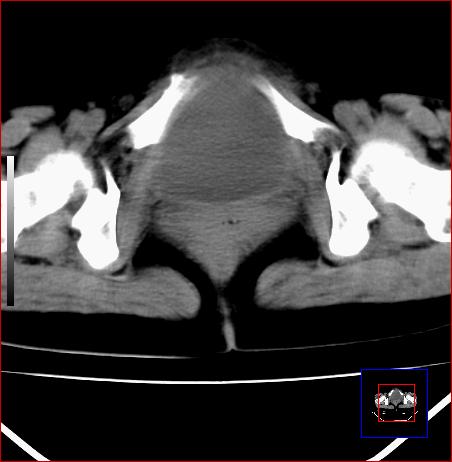

标题: CT15141:子宫肌瘤还是卵巢肿瘤 [打印本页]

腹部包块1年余,近两月明显增大,月经量多

病灶呈实性包块,边界清晰,似与子宫分界不清,考虑:子宫肌瘤

子宫体积增大,内密度不均匀。边缘清晰。考虑子宫肌瘤。

病灶呈实性包块,边界清晰,似与子宫分界不清,考虑:子宫肌瘤可能性大。其他待排